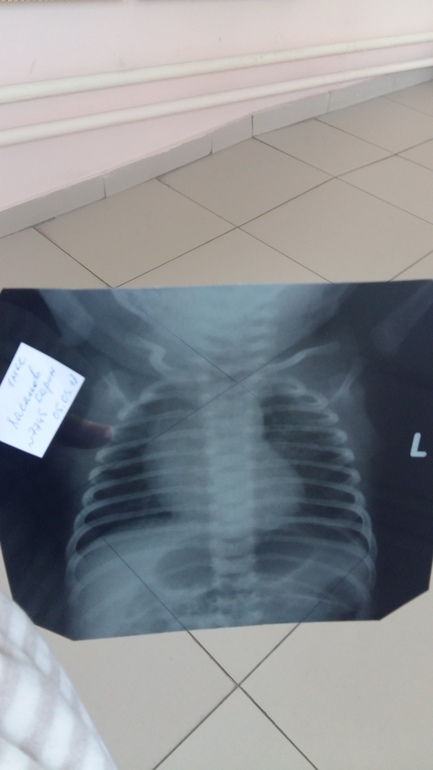

Покормила голодного страдальца и мы отправились на рентген. Это был архидлинный переход к другому зданию. Я не поленилась и посчитала на обратном пути - 212 метров😃

Рентген. Подхожу к кабинету, а там табличка "вызвали в реанимацию" и ожидали мы долго-долго. Мне было интересно, как делают рентген малышам. Вот и посмотрела. На стол кладут деревянную горочку + матрасик. Ниже пупка оборачивают защитным слоем и я держу его за руки, он как бы полу висит. Благо эти пытки недолги. Щелк и готово.

Утром был обход и врач сказала, что если результаты рентгена будут нормальными, а малыш будет реагировать на лечение, то нас отпустят.

С 8 марта! Как здорово, что вы дома! Главное, что легкие чистые, теперь массаж и ингаляции вылечат его окончательно!